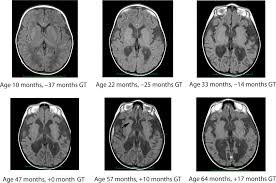

Long Term Follow Up After Gene Therapy For Canavan Disease Science Translational Medicine